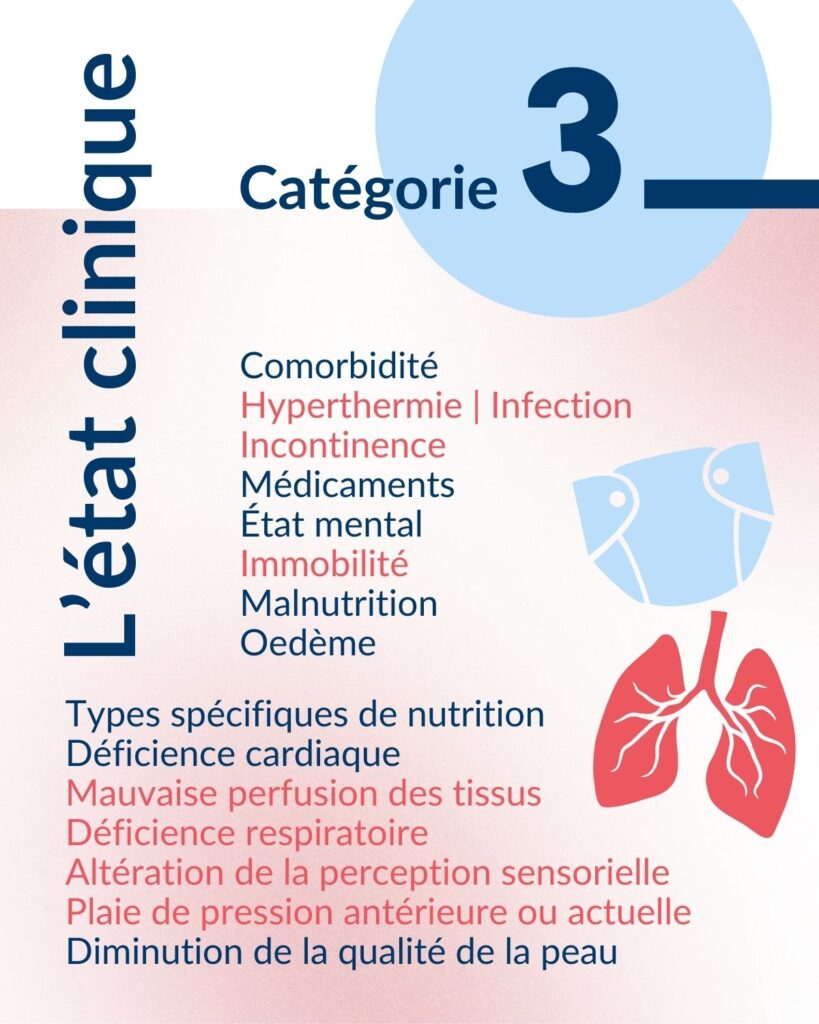

Les multiples facteurs de risque derrière les plaies de pression

Une synthèse de la littérature existante a permis d’identifier les multiples facteurs personnels associés à l’apparition des plaies de pression et de mesurer leur importance.